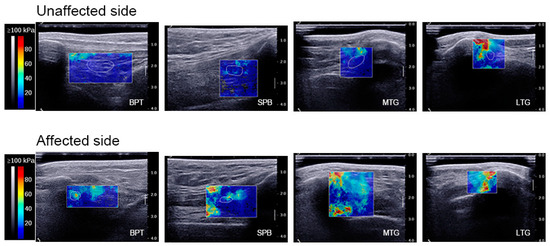

| SWE values of BPT (kPa) | 0° KF | 16.04 ± 11.84 | 34.04 ± 11.52 |

| 30° KF | 17.13 ± 13.75 | 39.41 ± 18.38 | |

| 60° KF | 26.76 ± 21.96 | 68.63 ± 33.63 | |

| 90° KF | 30.46 ± 23.51 | 122.93 ± 42.50 | |

| SWE values of the SPB (kPa) | 0° KF | 21.35 ± 12.96 | 28.21 ± 11.41 |

| 30° KF | 29.00 ± 10.81 | 51.49 ± 19.96 | |

| 60° KF | 41.44 ± 29.32 | 98.74 ± 47.27 | |

| 90° KF | 47.52 ± 16.18 | 108.32 ± 45.25 | |

| SWE values of the MTG (kPa) | 0° KF | 25.98 ± 13.90 | 39.57 ± 14.80 |

| 30° KF | 25.92 ± 7.30 | 53.62 ± 18.58 | |

| 60° KF | 36.06 ± 13.88 | 72.60 ± 30.68 | |

| 90° KF | 41.05 ± 13.65 | 85.58 ± 20.40 | |

| SWE values of the LTG (kPa) | 0° KF | 34.68 ± 15.24 | 55.82 ± 20.93 |

| 30° KF | 48.25 ± 26.16 | 81.77 ± 31.97 | |

| 60° KF | 56.34 ± 25.12 | 94.92 ± 34.93 | |

| 90° KF | 64.00 ± 31.86 | 107.19 ± 35.71 | |